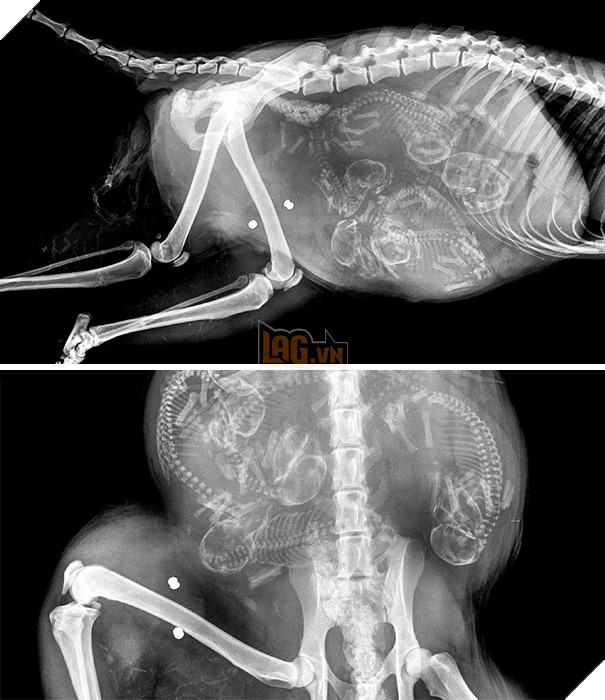

Trông có vẻ như các bé cún rất đông mà bụng chó mẹ thì lại chật hẹp. Thời gian thai của những chú cún hình thành và làm tổ ở sừng tử cung cho tới khi ra đời là khoảng 58 - 68 ngày (trung bình là 9 tuần). Những chú chó càng ít thai (dưới 4 con) thì thời gian mang thai càng dài.